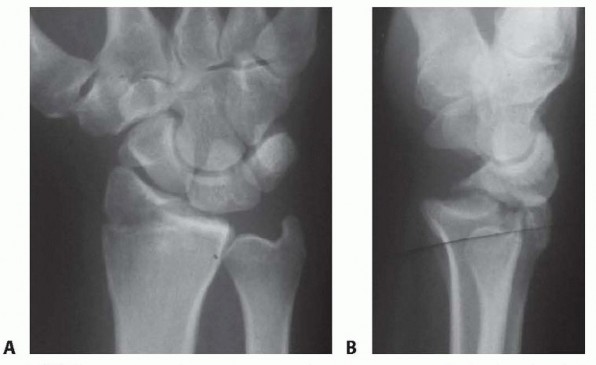

a DEFINITION Distal radius fractures occur at the distal end of the bone, originating in the metaphyseal regi…

DEFINITION A bimodal age distribution exists for patients with distal radius fractures (ie, young adults vs. …

f DEFINITION Fragment-specific fixation is a treatment approach for complex articular fracture patterns chara…